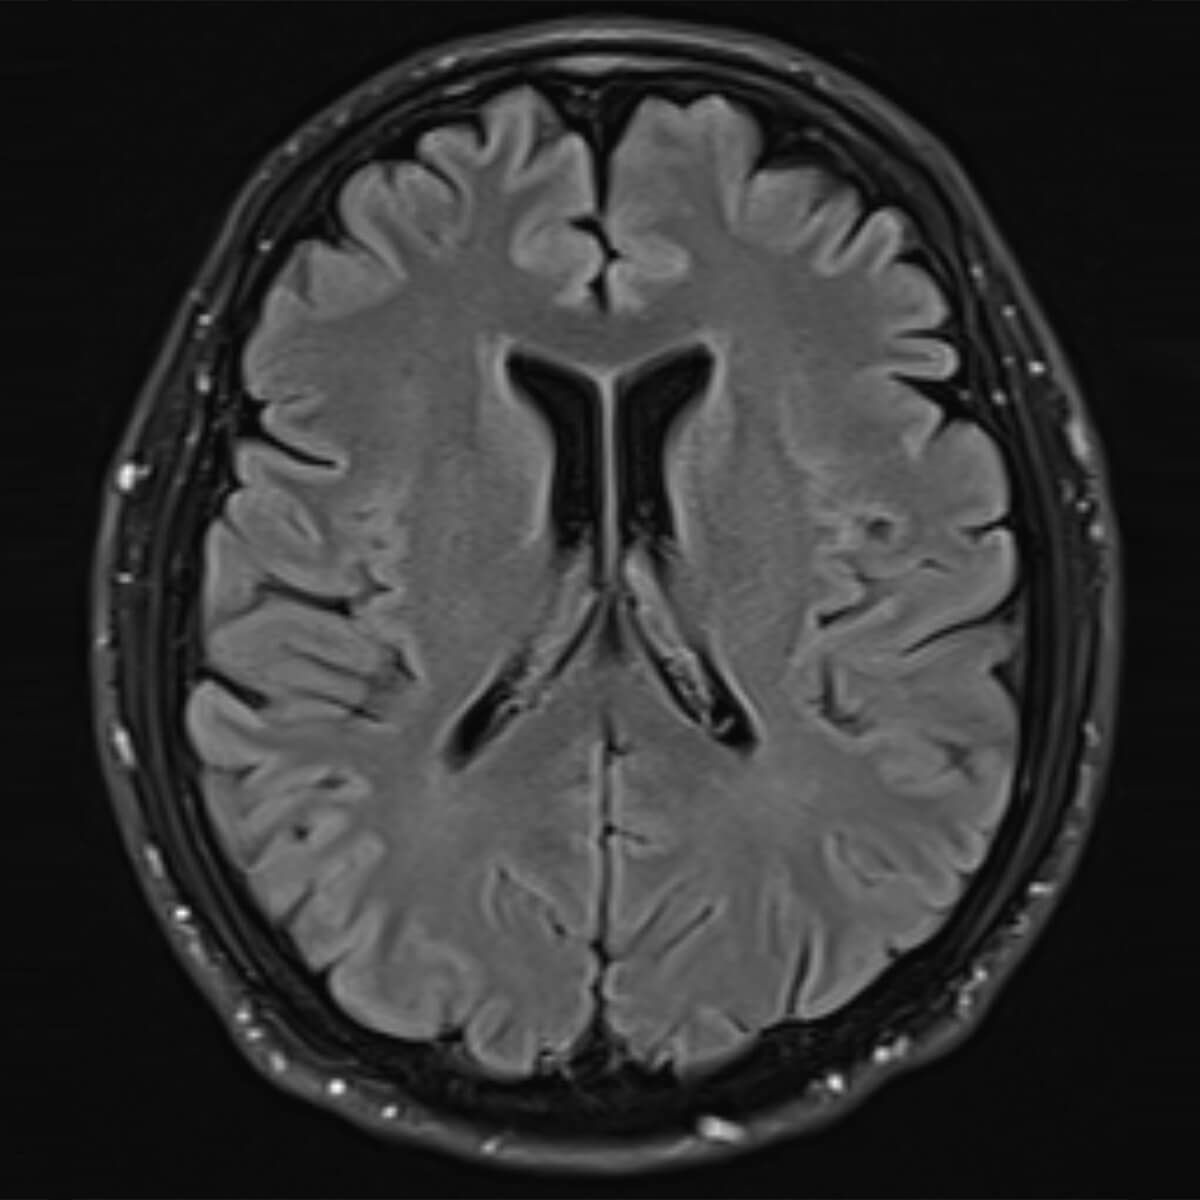

Basisabklärung z. B. bei Kopfschmerzen oder Schwindel. Bei komplexeren neurologischen Problemen würden wir einen Neuroradiologen hinzuziehen. Zudem bieten wir Untersuchungen im Bereich der Nasennebenhöhlen und der Speicheldrüsen an, z. B. bei V.a. (chronische) Sinusitis oder V.a. Speicheldrüsensteine.